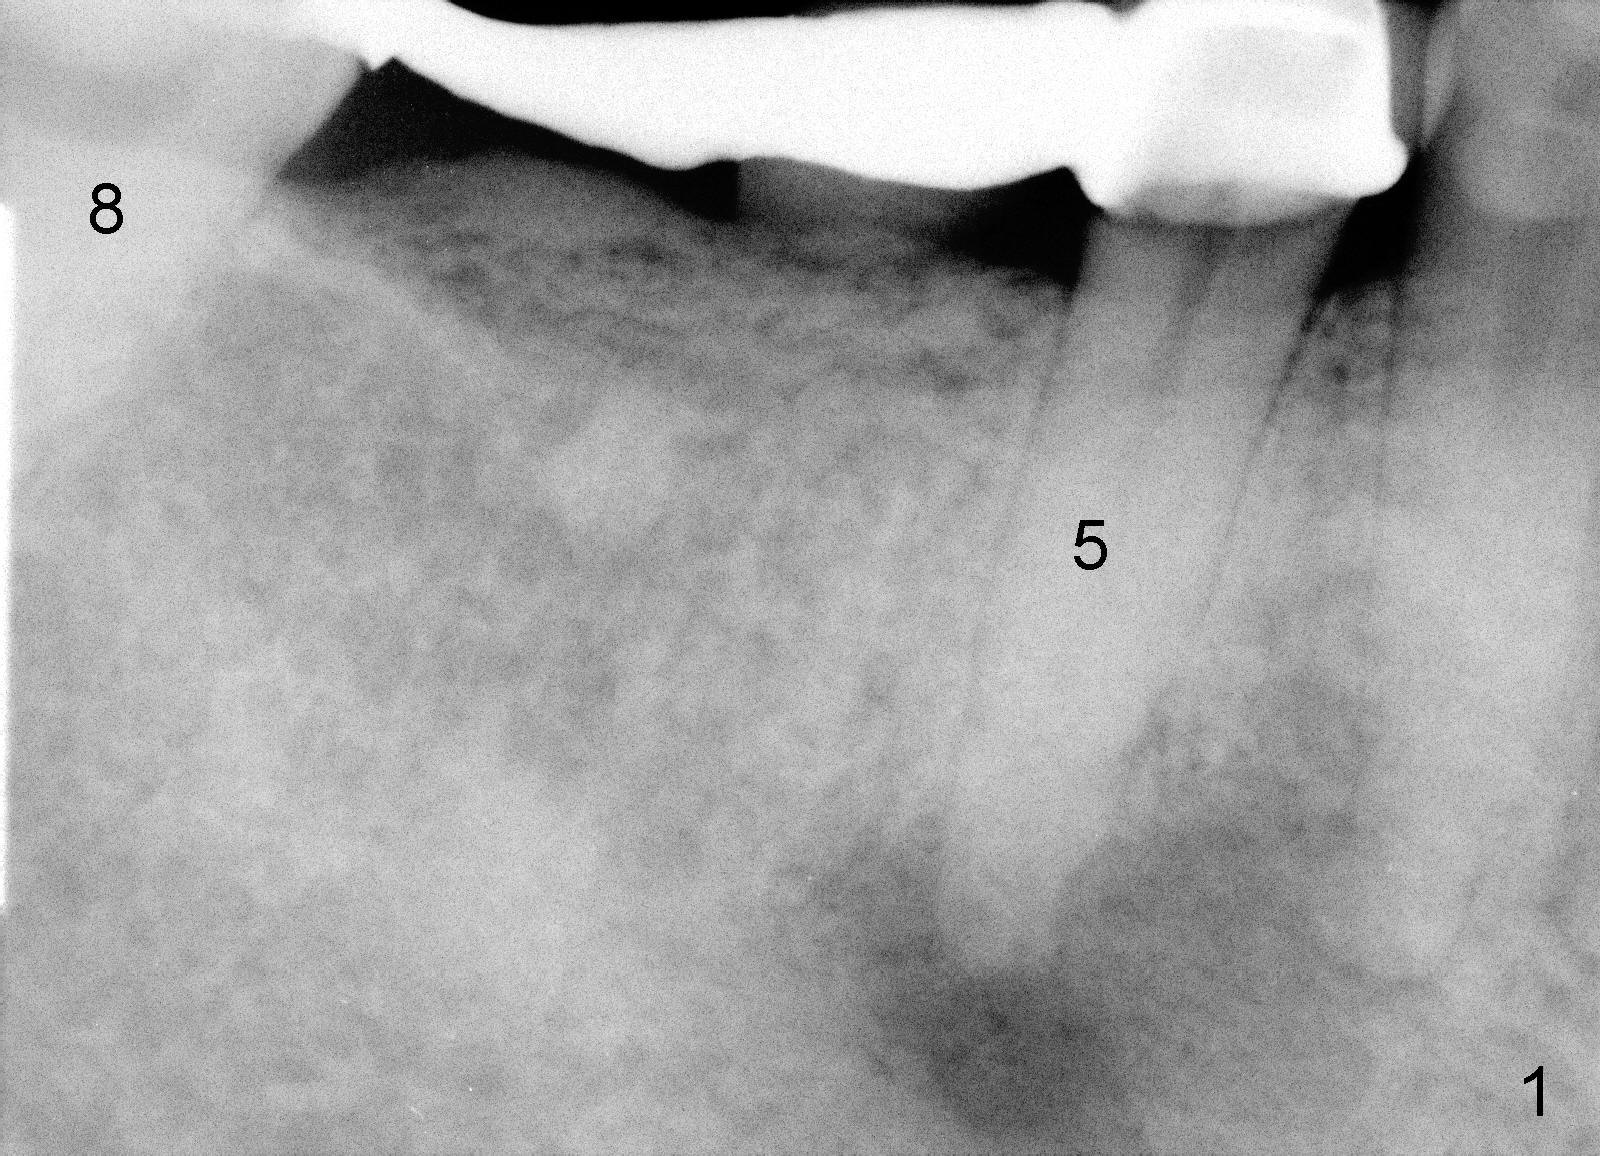

A 49-year-old lady cannot chew with the lower right bridge (Fig.1: from the 2nd premolar (5) to the third molar (8)). Insertion of gutta percha (Fig.2 >) points to the apical radiolucency of the anterior abutment (*). The bridge is sectioned between the pontic of 2nd molar and the retainer of the posterior abutment. The anterior segment of the bridge falls out. The anterior abutment is non-salvageable due to severe 2nd caries (Fig.3 (5) part of panaramic X-ray). The yellow lines denote the inferior alveolar nerve. In brief, the apex of the affected tooth is most likely closely associated with the mental loop.